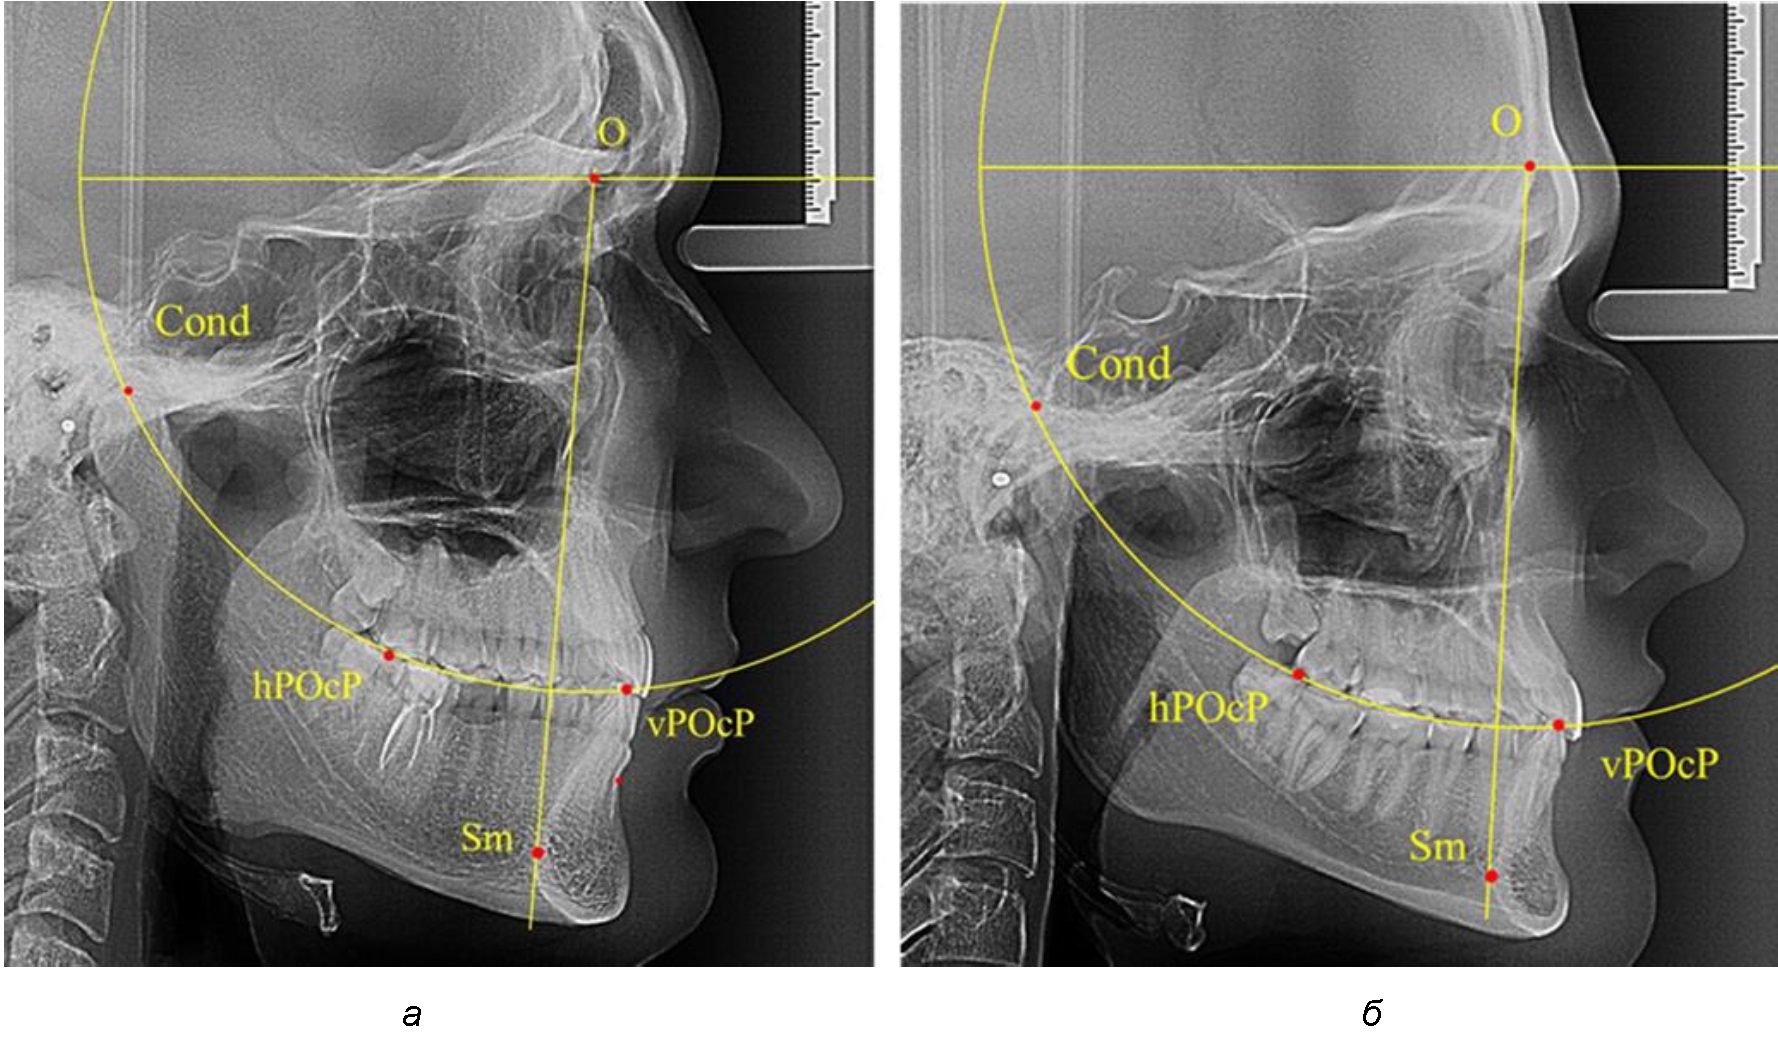

В группе рентгенограмм с ретрузионным положением резцов также проводилось распределение на подгруппы с учетом широтных размеров подбородочного выступа.

Анализ результатов показал, что практически при всех вариантах подбородочного выступа в данной группе исследования первые премоляры, как правило, располагались либо на стресс-оси Bimler, либо позади. Рентгенограммы пациентов с ретрузионным положением резцов при широком и среднем варианте подбородочного выступа представлены на рис. 4.

Таким образом, для людей с ретрузионным типом зубочелюстных дуг характерно расположение первых премоляров позади стресс-оси либо на средней линии, и этот показатель не может быть использован в качестве выбора метода лечения аномалий для данной группы исследования вне зависимости от формы подбородочного выступа.

Рис. 4. Положение первых верхних премоляров при ретрузии с широкими (а) и средними (б) размерами подбородка

Результаты проведенного исследования показали зависимость расположения первых премоляров от положения передних зубов и вариабельности расположения межрезцовой точки. Отмечено, что при протрузионном положении резцов у людей с физиологическим прикусом смещение первых премоляров кпереди от стресс-оси Bimler не может быть показанием к удалению первых премоляров при патологической окклюзии с однотипными зубными дугами. В то же время расположение первых верхних премоляров позади или на линии Bimler у людей с ретрузинным типом дуг также не является противопоказанием к экстракционным методам лечения.

Ширина подбородочного выступа также оказывает влияние на положение стресс-оси Bimler.